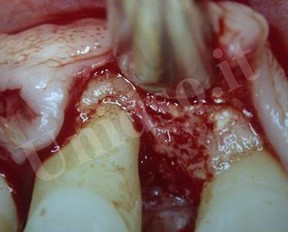

L’ Unità Operativa di Parodontologia e Igiene Orale si compone di 5 sezioni. L’attività’ clinico-assistenziale è svolta da diversi odontoiatri, supportata da igienisti dentali e assistenti alla poltrona, ed è articolata sulla base di appuntamenti programmati. Nell’Unità Operativa di Paradontologia e Igiene Orale del DSMOB si eseguono le seguenti prestazioni odontoiatriche: istruzioni d’igiene orale, ablazione tartaro, full radiografico, terapia dell’alitosi, levigatura radicolare, chirurgia parodontale riparativa, resettiva e rigenerativa e chirurgia plastica dei tessuti molli parodontali.